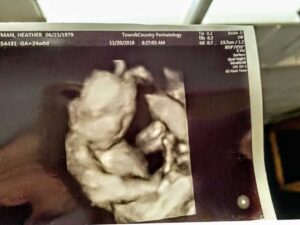

My chances of both sticking and having twins was less than 5%. Two weeks later, I got that beautiful POSITIVE. I was pregnant and I had the blood tests to confirm it! I kept praying that it was one baby so that I’d have the best chance of moving forward. I was scared out of my mind when I heard the word TWINS at my 6-week ultrasound.

The first two weeks, they found two sacs but only one heartbeat. The docs were sure the baby would not survive. ‘It may just be one,’ they told me. Just when I started to wrap my head around this, I went back in for more testing at 8 weeks. ‘There’s two little strong heartbeats,’ they told me. So, I came to terms with having twins again. This time I was going to do this!